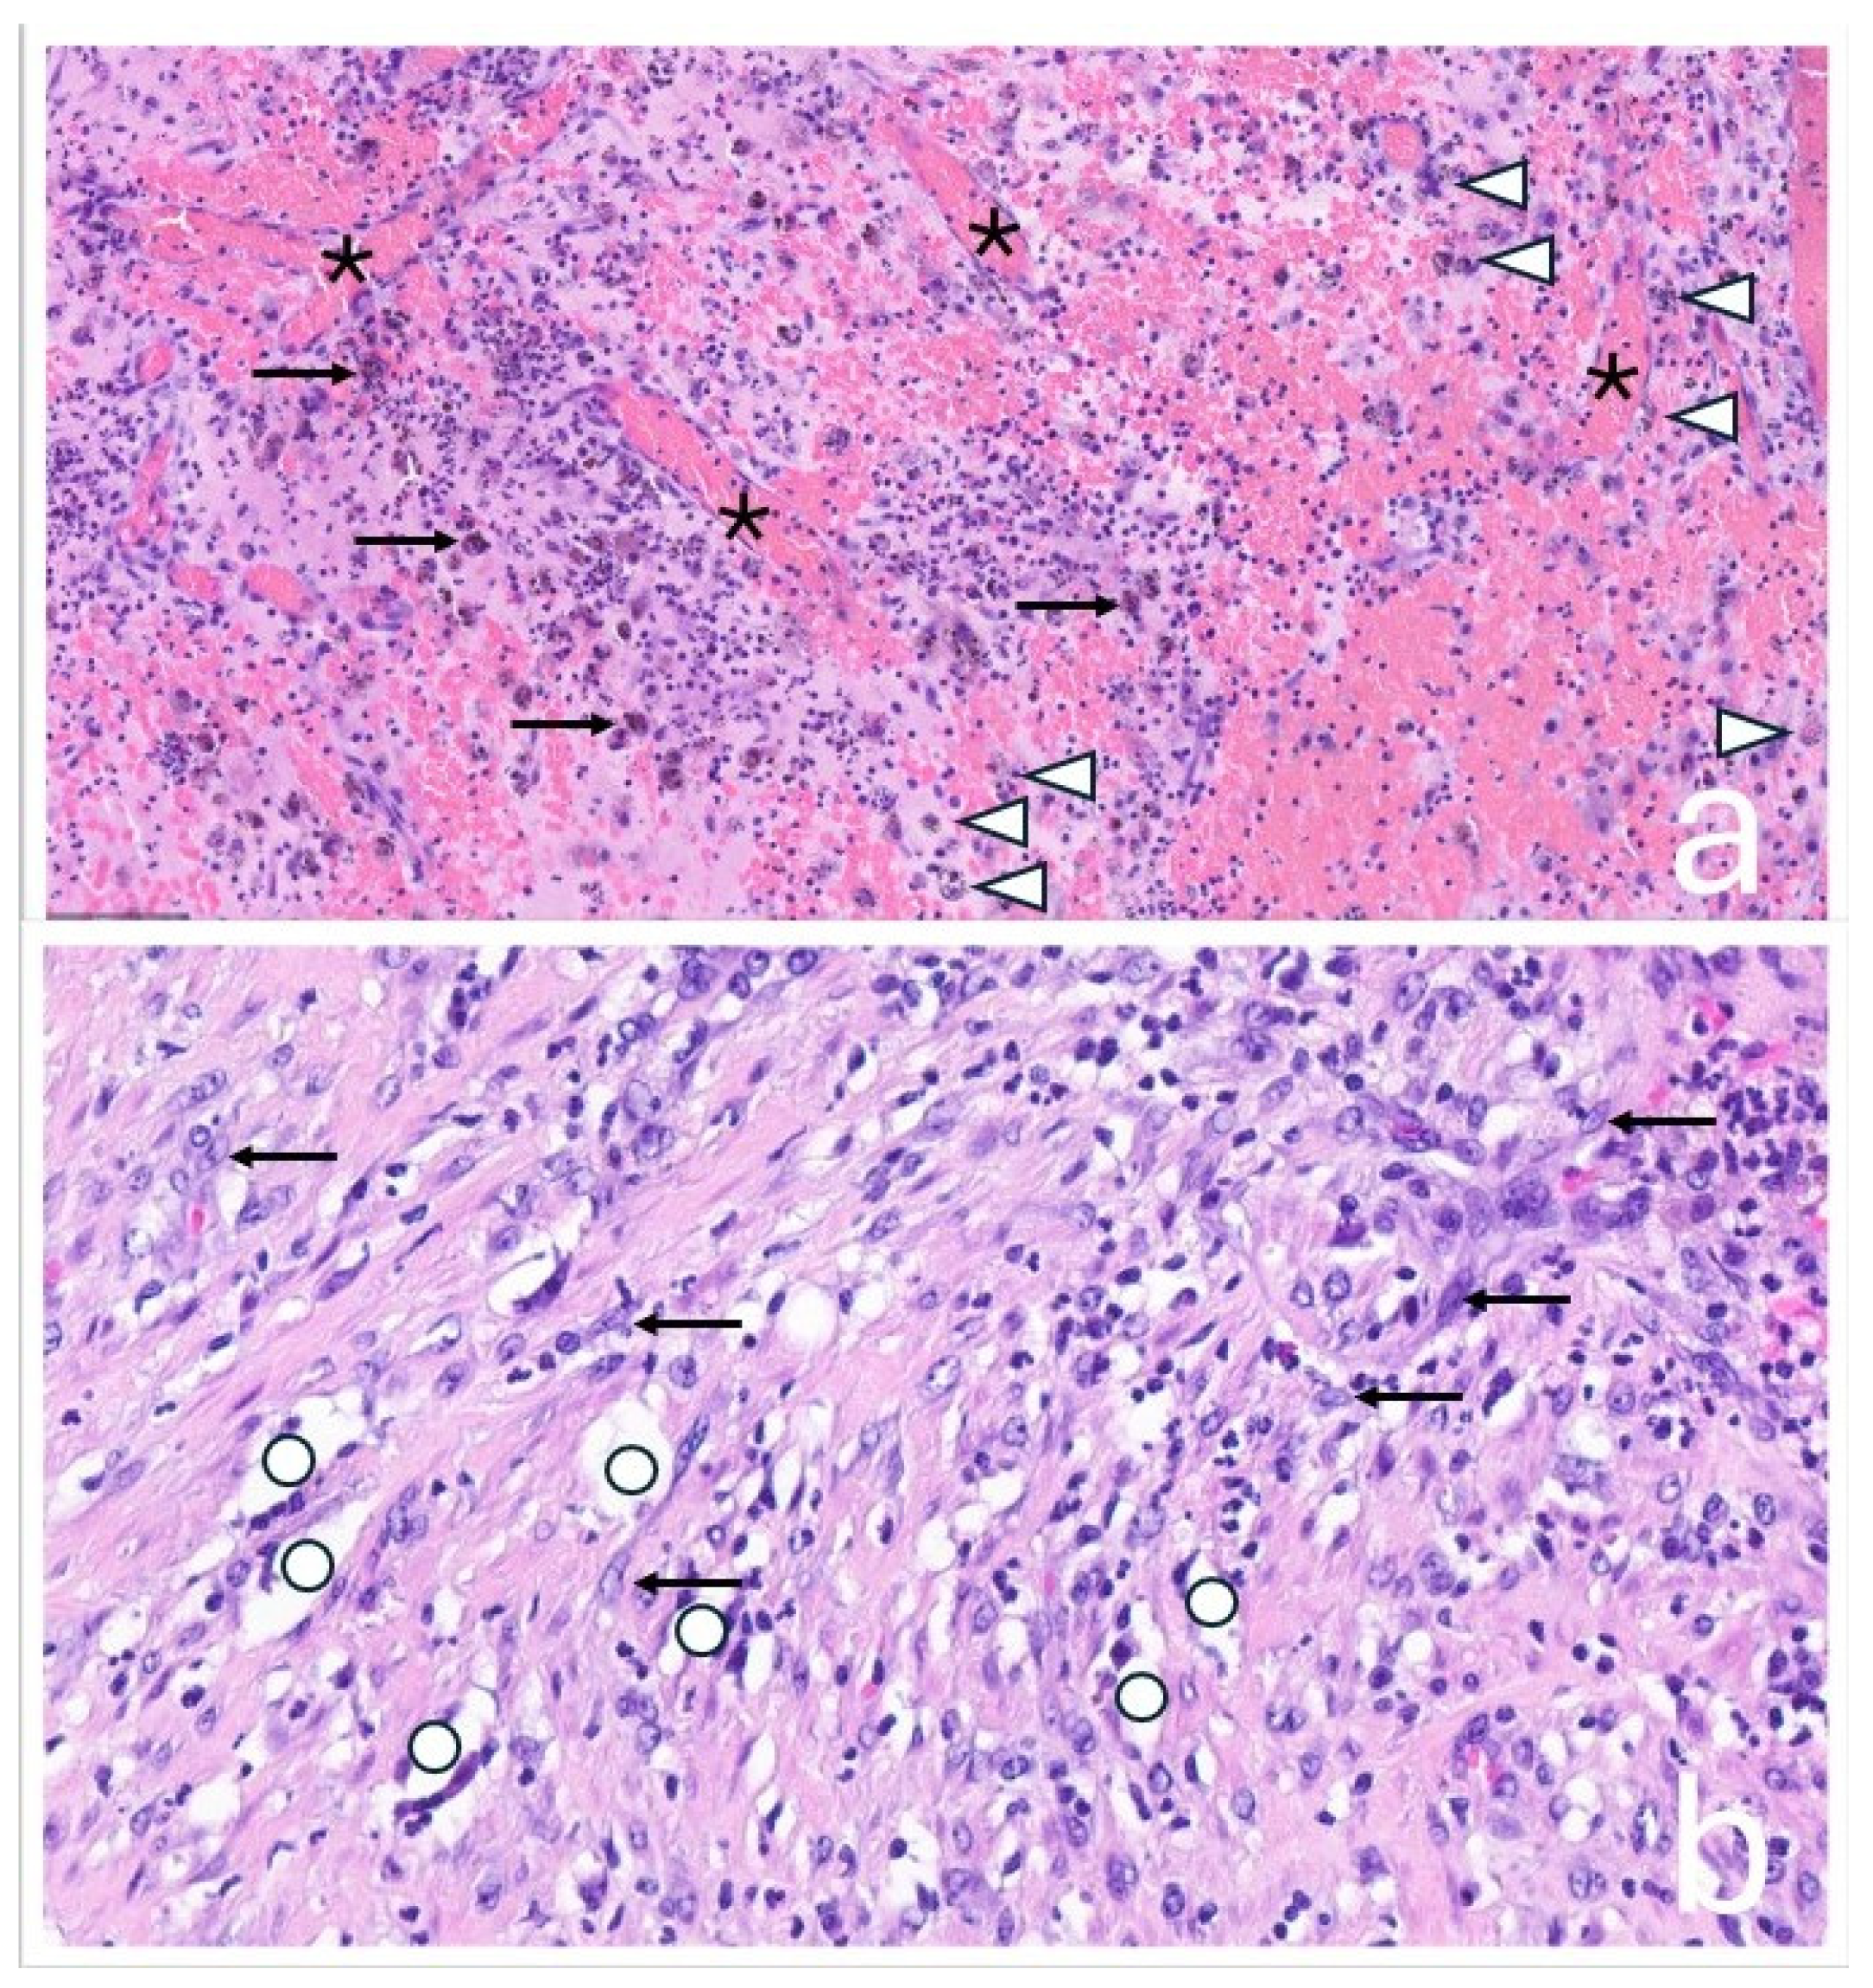

In 2017, a revision surgery was performed in the same hospital due to persistent hip joint pain and radiologically evident eccentric wear of the liner in the primary load-bearing zone. The liner was replaced with highly cross-linked polyethylene and a new metal head (Figure 3).

Figure 3. (a) The eccentric position of the prosthetic head is visible, indicating wear-related reaction of the sandwich-type inlay (metal shell encased in a polyethylene liner) in the main load-bearing zone. Additionally, heterotopic ossifications around the hip joint are observed. (b) The condition after the head/inlay exchange. The new metal head is now centrally positioned in the cross-linked polyethylene insert.